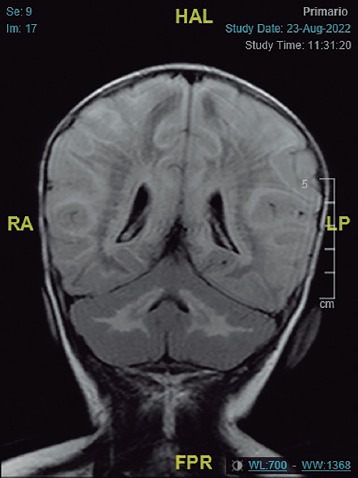

Case report: A 7-month-old male infant with no relevant history was admitted to a tertiary hospital as a result of vomiting, refusing food, and neurological symptoms. The episode was diagnosed as subacute rhombencephalitis based on the clinical findings and brain magnetic resonance imaging. Treatment with corticotherapy was undertaken, and led to gradual improvement. The patient was admitted once again three months later, due to an evident neurological regression after vaccination. A further MRI brain scan showed findings compatible with leukodystrophy, which was diagnosed as leukoencephalopathy with vanishing white matter after a genetic study. Treatment of symptoms was undertaken with follow-up by the home hospitalisation unit. However, the patient finally died at 15 months of age as a consequence of the evolution of his condition.